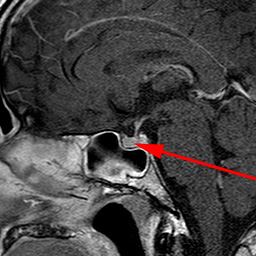

Hypofyse, normal, MR

MR optagelse af normal hypofyse (rød pil) fra siden.